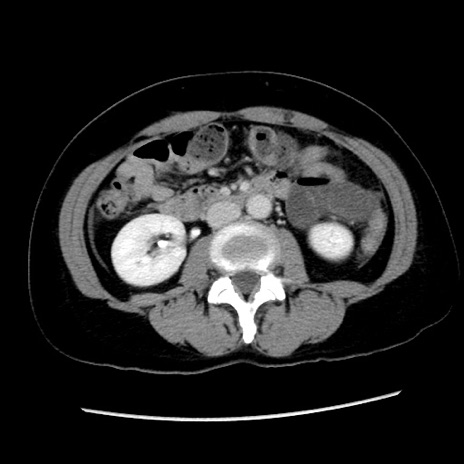

冠状断像

【症例】 50歳代女性

【主訴】 腹痛

【現病歴】前日生レバーを食べた。今朝に排便あり。 昼前に突然発症の腹痛を生じ、当院救急外来を受診した。

【既往歴】 子宮筋腫にてで子宮全摘後

【身体所見】 意識清明、腹部:平坦、軟、下腹部やや左を中心に圧痛・反跳痛あり、筋性防御あり

【データ】WBC 7800、CRP 0.07